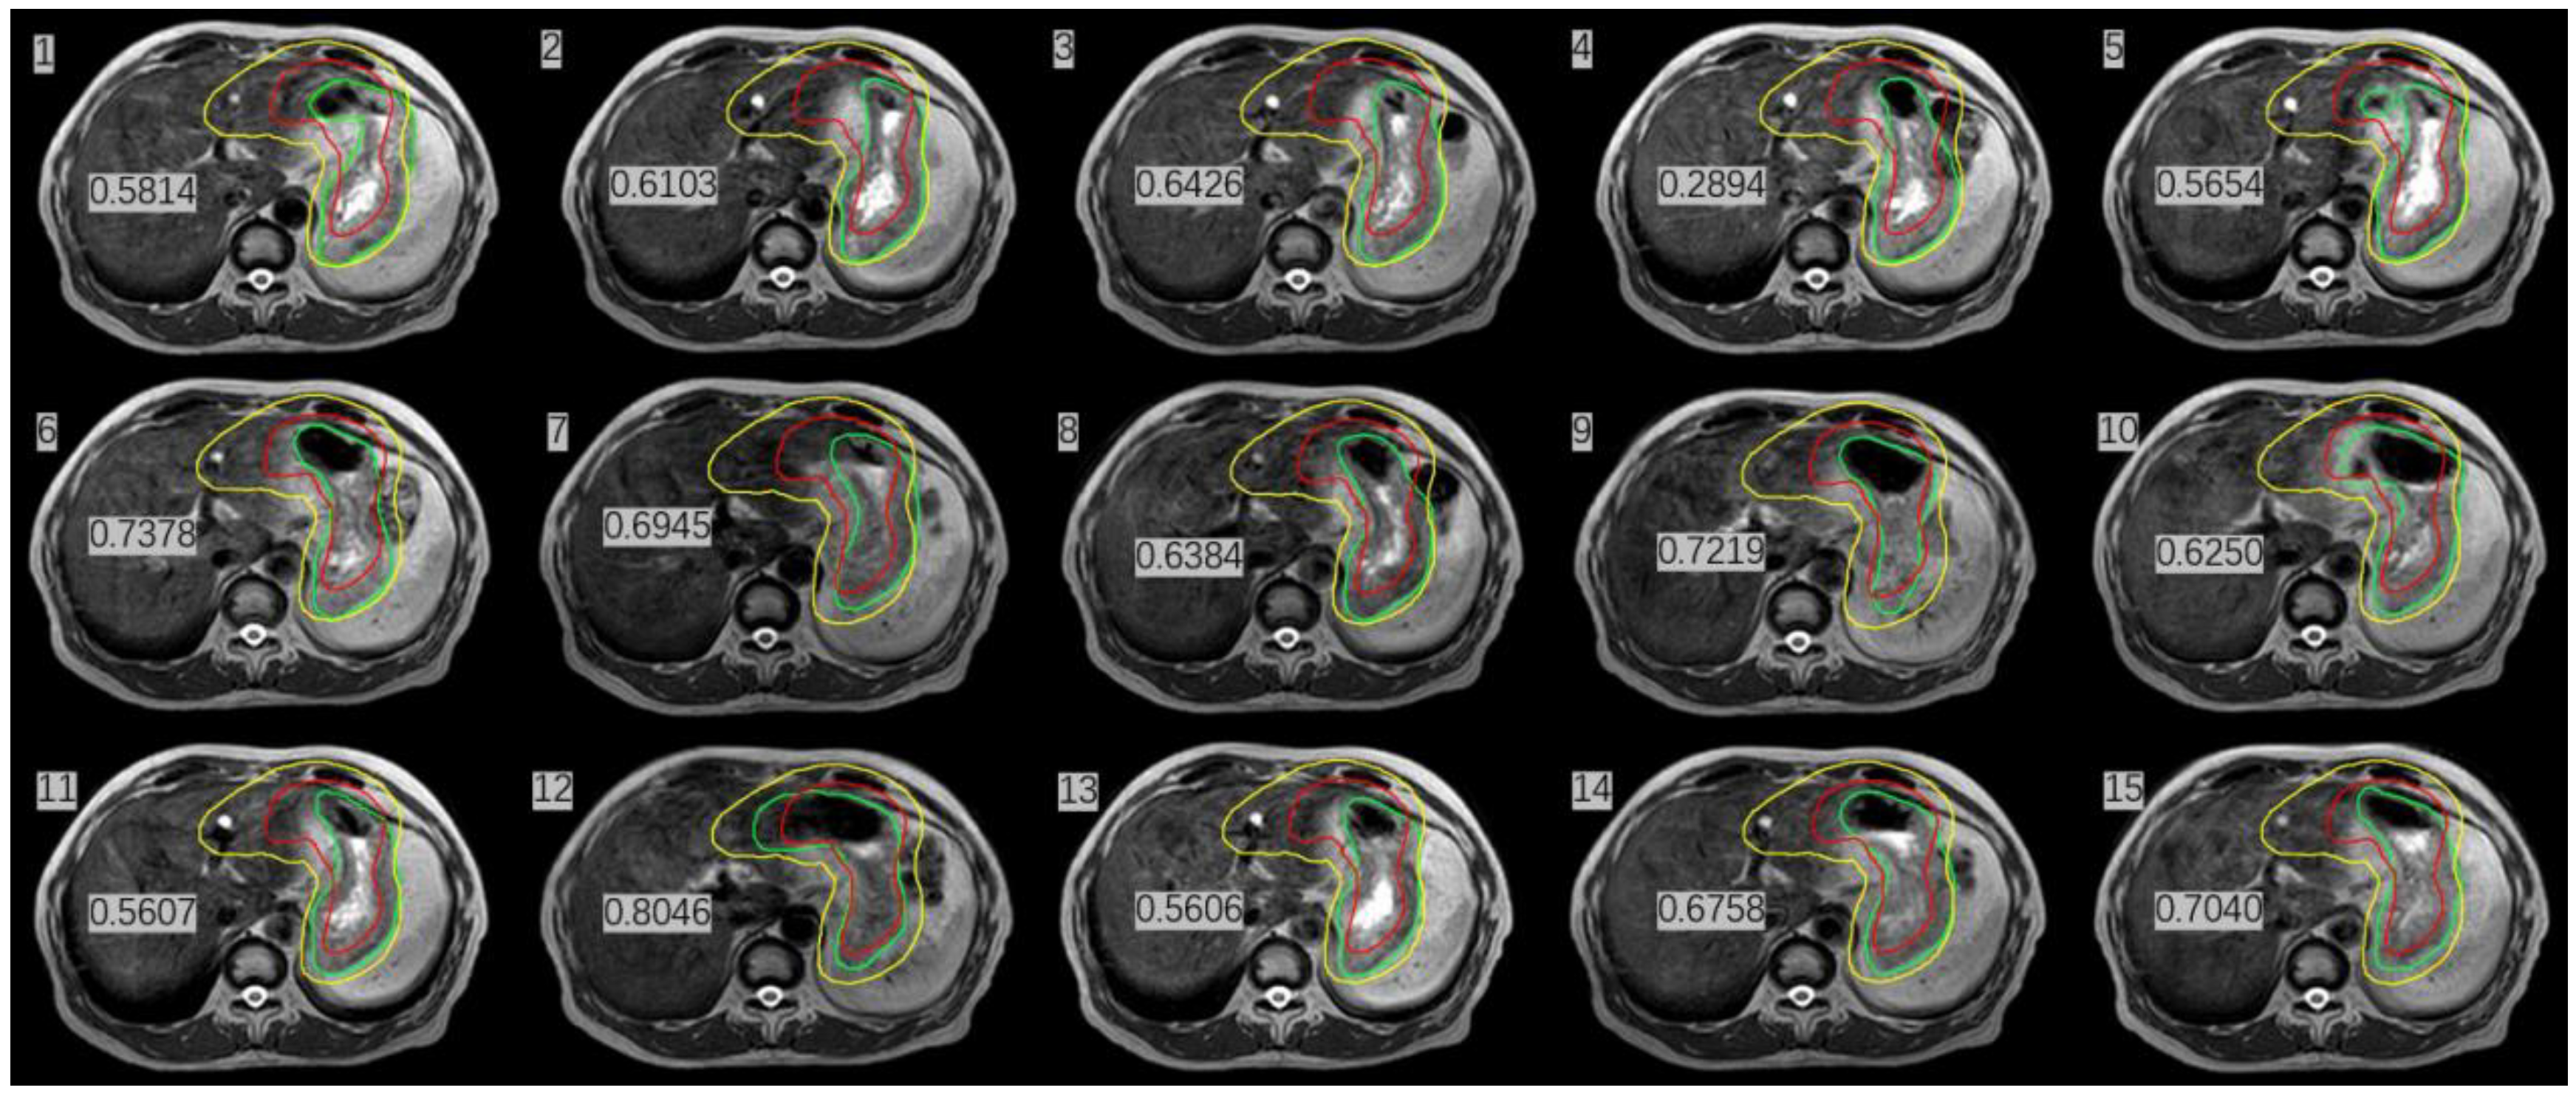

Figure 4.

Stomach delineation DSC (number in Figure) of real-time MR imaging and simulation CT imaging the (red line delineates the stomach on the simulation images, the green line delineates the stomach on the daily MRI images, and the yellow line delineates the stomach considering 1 cm external expansion from the iCTV).

We calculated the DSC after stomach delineation of real-time MR imaging and simulation CT imaging. Interestingly, we found that the patient’s inter-fractional stomach variation changed greatly. With CBCT online guidance, even after expanding the PTV by 1 cm as usual, there remain 8/15 axis planes that could not cover the entire stomach; therefore, the target, i.e., the entire stomach, would be missed (Figure 4) At the same time, we could monitor the organs around the stomach, such as liver, left kidney, and spinal cord, which were irradiated daily, and compared their state them with that of the same organs after a mean dose in the CT simulation. (Table 1) The liver and duodenum were on average less exposed to toxic doses in each MRI-guided treatment than in the CT simulation (liver: 840.7 cGy < 929.1 cGy, duodenum: 874.9 cGy < 1025.1 cGy). Although the average doses received by the spinal cord and the left kidney were slightly higher in MRI-guided therapy than in CT simulation (spinal cord:483.3 cGy > 470.8 cGy, left kidney: 297.7 cGy > 277.7 cGy), they were far lower than their respective dose constraints (the maximum dose constraint for the spinal cord is 4500 cGy, and the average kidney dose constraint is less than 1800 cGy) [8].

IGRT has become routine as a standard configuration in modern radiation therapy. Imaging the patient prior to treatment can help reduce the impact of setup errors, thus improving the dose delivery accuracy [13]. Currently, most modern radiotherapy systems are equipped with kV CBCT to visualize anatomical structures and identify the target volumes. Although CBCT is highly effective, it provides images with poor quality for soft tissues—including abdominal organs such as the liver, stomach, and pancreas—which makes it very difficult to accurately identify the soft-tissue targets and surrounding OARs. In the case of our gastric MALT lymphoma patient shown in Figure 5, it was not feasible to use CBCT for image guidance because of its poor image quality. A larger PTV margin with at least 1 cm had to be delineated, but this would cause higher toxicity to OARs. In addition, a 1 cm margin could not cover the entire empty stomach even if anisodamine (dose 10 mg) was administered to reduce gastric motility (Figure 4) [14] (pp. 174–177). As shown in Figure 4, even after expanding the PTV by 1 cm as usual with CBCT online guidance, there remain 8/15 axis planes that could not cover the entire stomach. Therefore, the target, i.e., the entire stomach, would be missed in regular clinical practice without MRI image guidance. Poor CBCT imaging of the stomach makes it more challenging to incorporate corrections for certain differences in routine patient anatomy, as well as to use approaches based on adaptive treatment protocols. The MR-LINAC system overcomes the limitations of traditional IGRT, especially for soft tissues requiring the precise definition of the target and of OARs. MR-LINAC improves IGRT by enhancing soft-tissue contrast in MR images without delivering concomitant radiation doses. MR-LINAC brings a unique emerging workflow that can help radiation therapy practitioners improve their skills and understand MR anatomy. The case reported here illustrates that MR-LINAC could visualize the stomach clearly, especially after administering anisodamine. Meanwhile, an attractive option for MR-LINAC might be to re-optimize or adjust the therapeutic plan before each radiation treatment. Diagnostic-quality MR images can be acquired based on the actual patient anatomy before and during treatment and then used in an online adaptive workflow. Compared to CBCT, online 1.5 T MRI provides better target visualization on an MR-LINAC and aids online adaptive treatment strategies, including daily replanning. Although online adaptation techniques guided by CBCT are improving, the quality of stomach images obtained by CBCT is likely to remain poor. In contrast, in MRI-guided therapy, increased soft-tissue contrast can more accurately visualize day-to-day variations and may allow the delineation of a smaller PTV margin, thus reducing OAR toxicity [15].